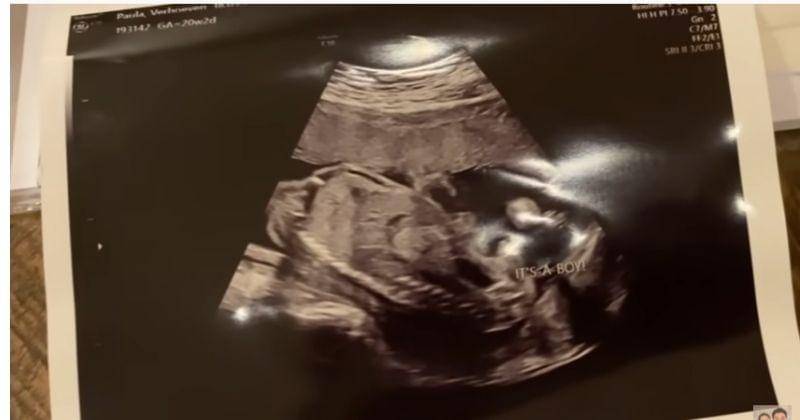

Sebelum mengetahui jenis kelamin anak keduanya, Baim Wong tampak melihat hasil pemeriksaan USG istrinya. Namun, Baim tidak langsung menyadari bahwa ada tulisan yang menginformasikan jenis kelamin anak keduanya.

Dia pun terkejut ketika mengetahui ada tulisan di hasil pemeriksaan USG istrinya.

"It's a boy," teriak Baim. Dia pun langsung memeluk istrinya sebagai ungkapan rasa bahagia mengetahui jenis kelamin anak keduanya.